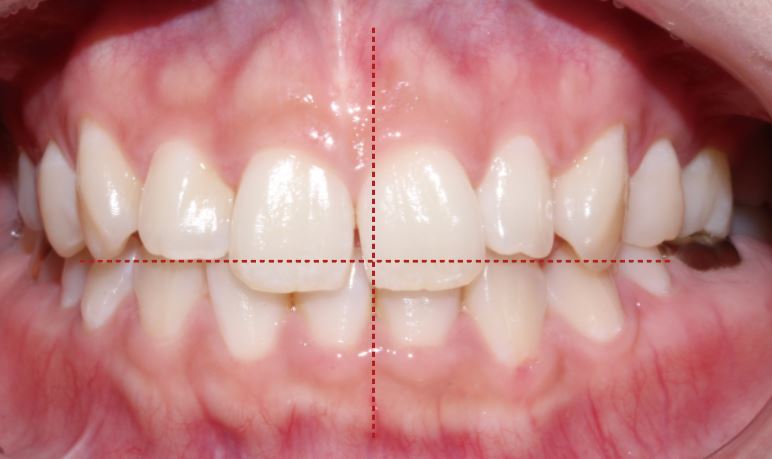

환자분의 상태는 체크해보면 상악 전치부 크기의

합이 상악보다 2mm정도 부족해요.

또한 앞니가 훨씬 더 길어 보이는 느낌이 들고

상악 중절치가 눈에 띄게 도드라져

보이는 케이스였어요.

상악의 중간 선과 하악의 중간선이 맞지 않고

기울어져 있는 걸 확인할 수 있어요-:D

그리고 상악 왼쪽에 있는 측절치의 사이즈가

평균 치아크기보다 조금 더 작더라고요.

확연하게 달라진 after 모습이 보이시나요?!

환자분께서 가장 고민이었던

"토끼 이빨처럼 크고 긴 앞니 " 가

클리피씨 전체 교정으로 눈에 띄게 개선이 되었어요.

상악 중철치 치축이 기울어져 있는 것도 많이

개선이 된 모습이에요♪